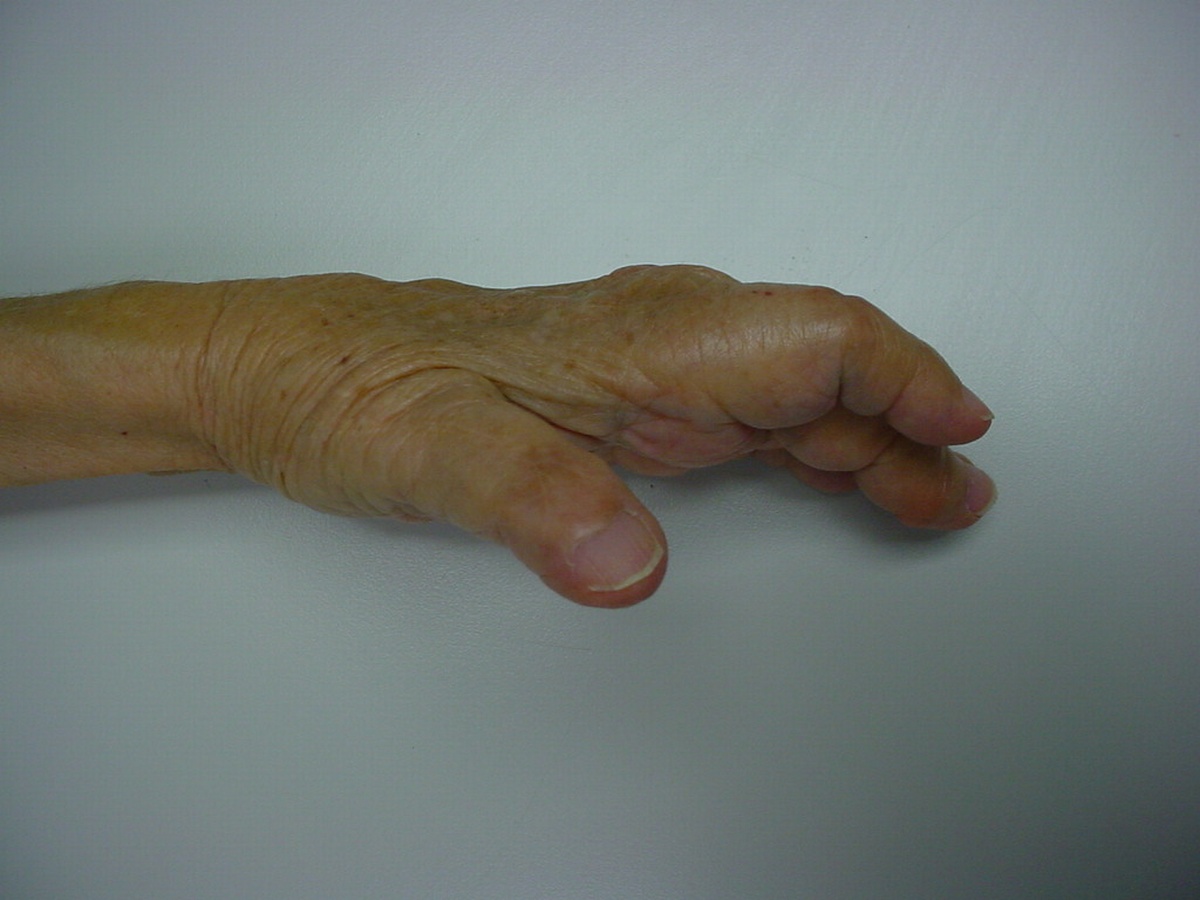

This woman has undergone multiple rheumatoid procedures elsewhere. On the right, these included right wrist fusion and MCP silicone arthroplasties. On the left, silicone arthroplaties of the thumb MCP, index and middle PIP joints and arthrodesis of the thumb IP, ring and small PIP koints. She wanted improvement of her left hand function, which was hindered by wrist pain and flail fingers.

Her left index and middle fingers are grossly unstable.

Her greatest desire was pinch reconstruction. This was approached in two stages: wrist fusion, implant removal and fusion of the index and middle PIP joints, followed by index and middle MCP arthroplasties. There are several alternative approaches, including index MCP fusion and revision PIP arthroplasties.